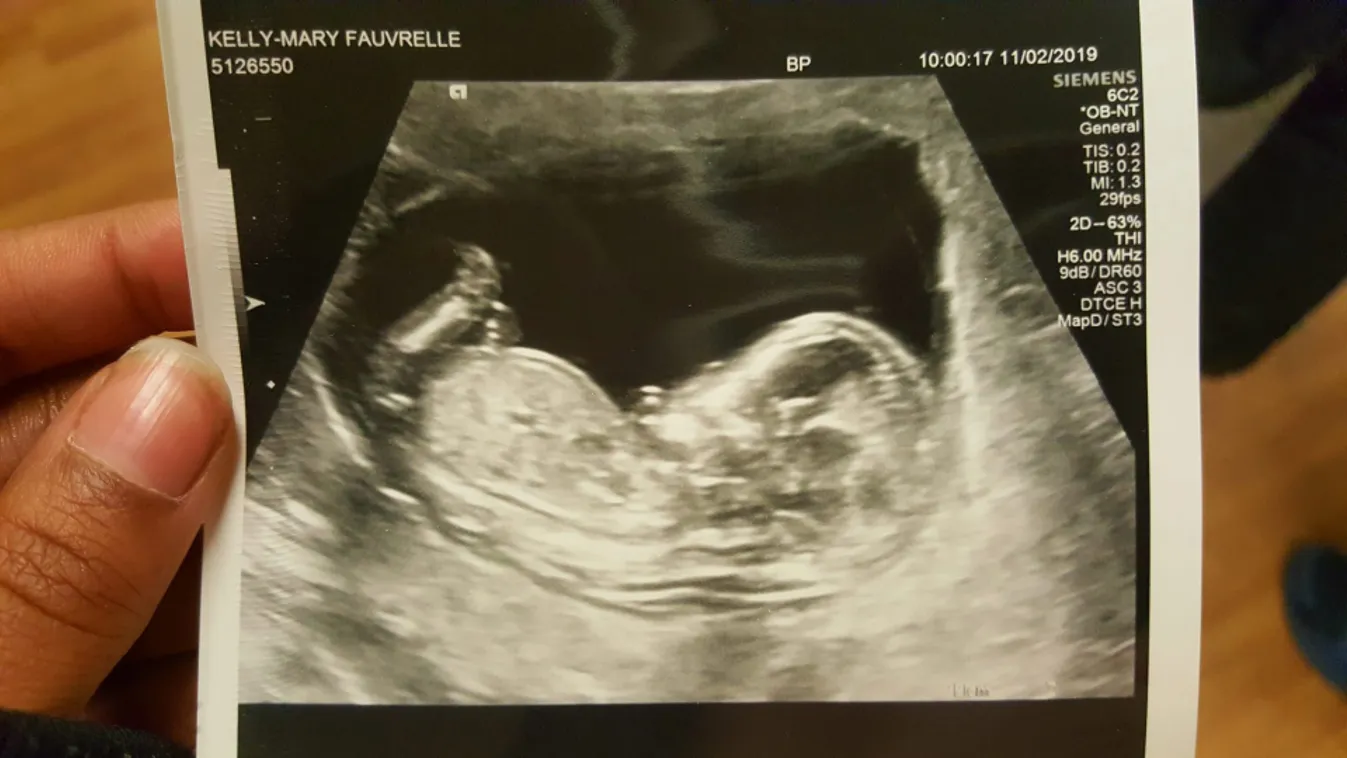

Fauvrelle (26) a gyilkosság napján éppen 33 hetes terhes volt. Szakításuk előtt Aaron és Fauvrelle több évig voltak egy pár. A várandós nő a földszinten lakott, szobájának ablaka a kertre nézett, így azon keresztül akadálytalanul bejuthatott gyilkosa.